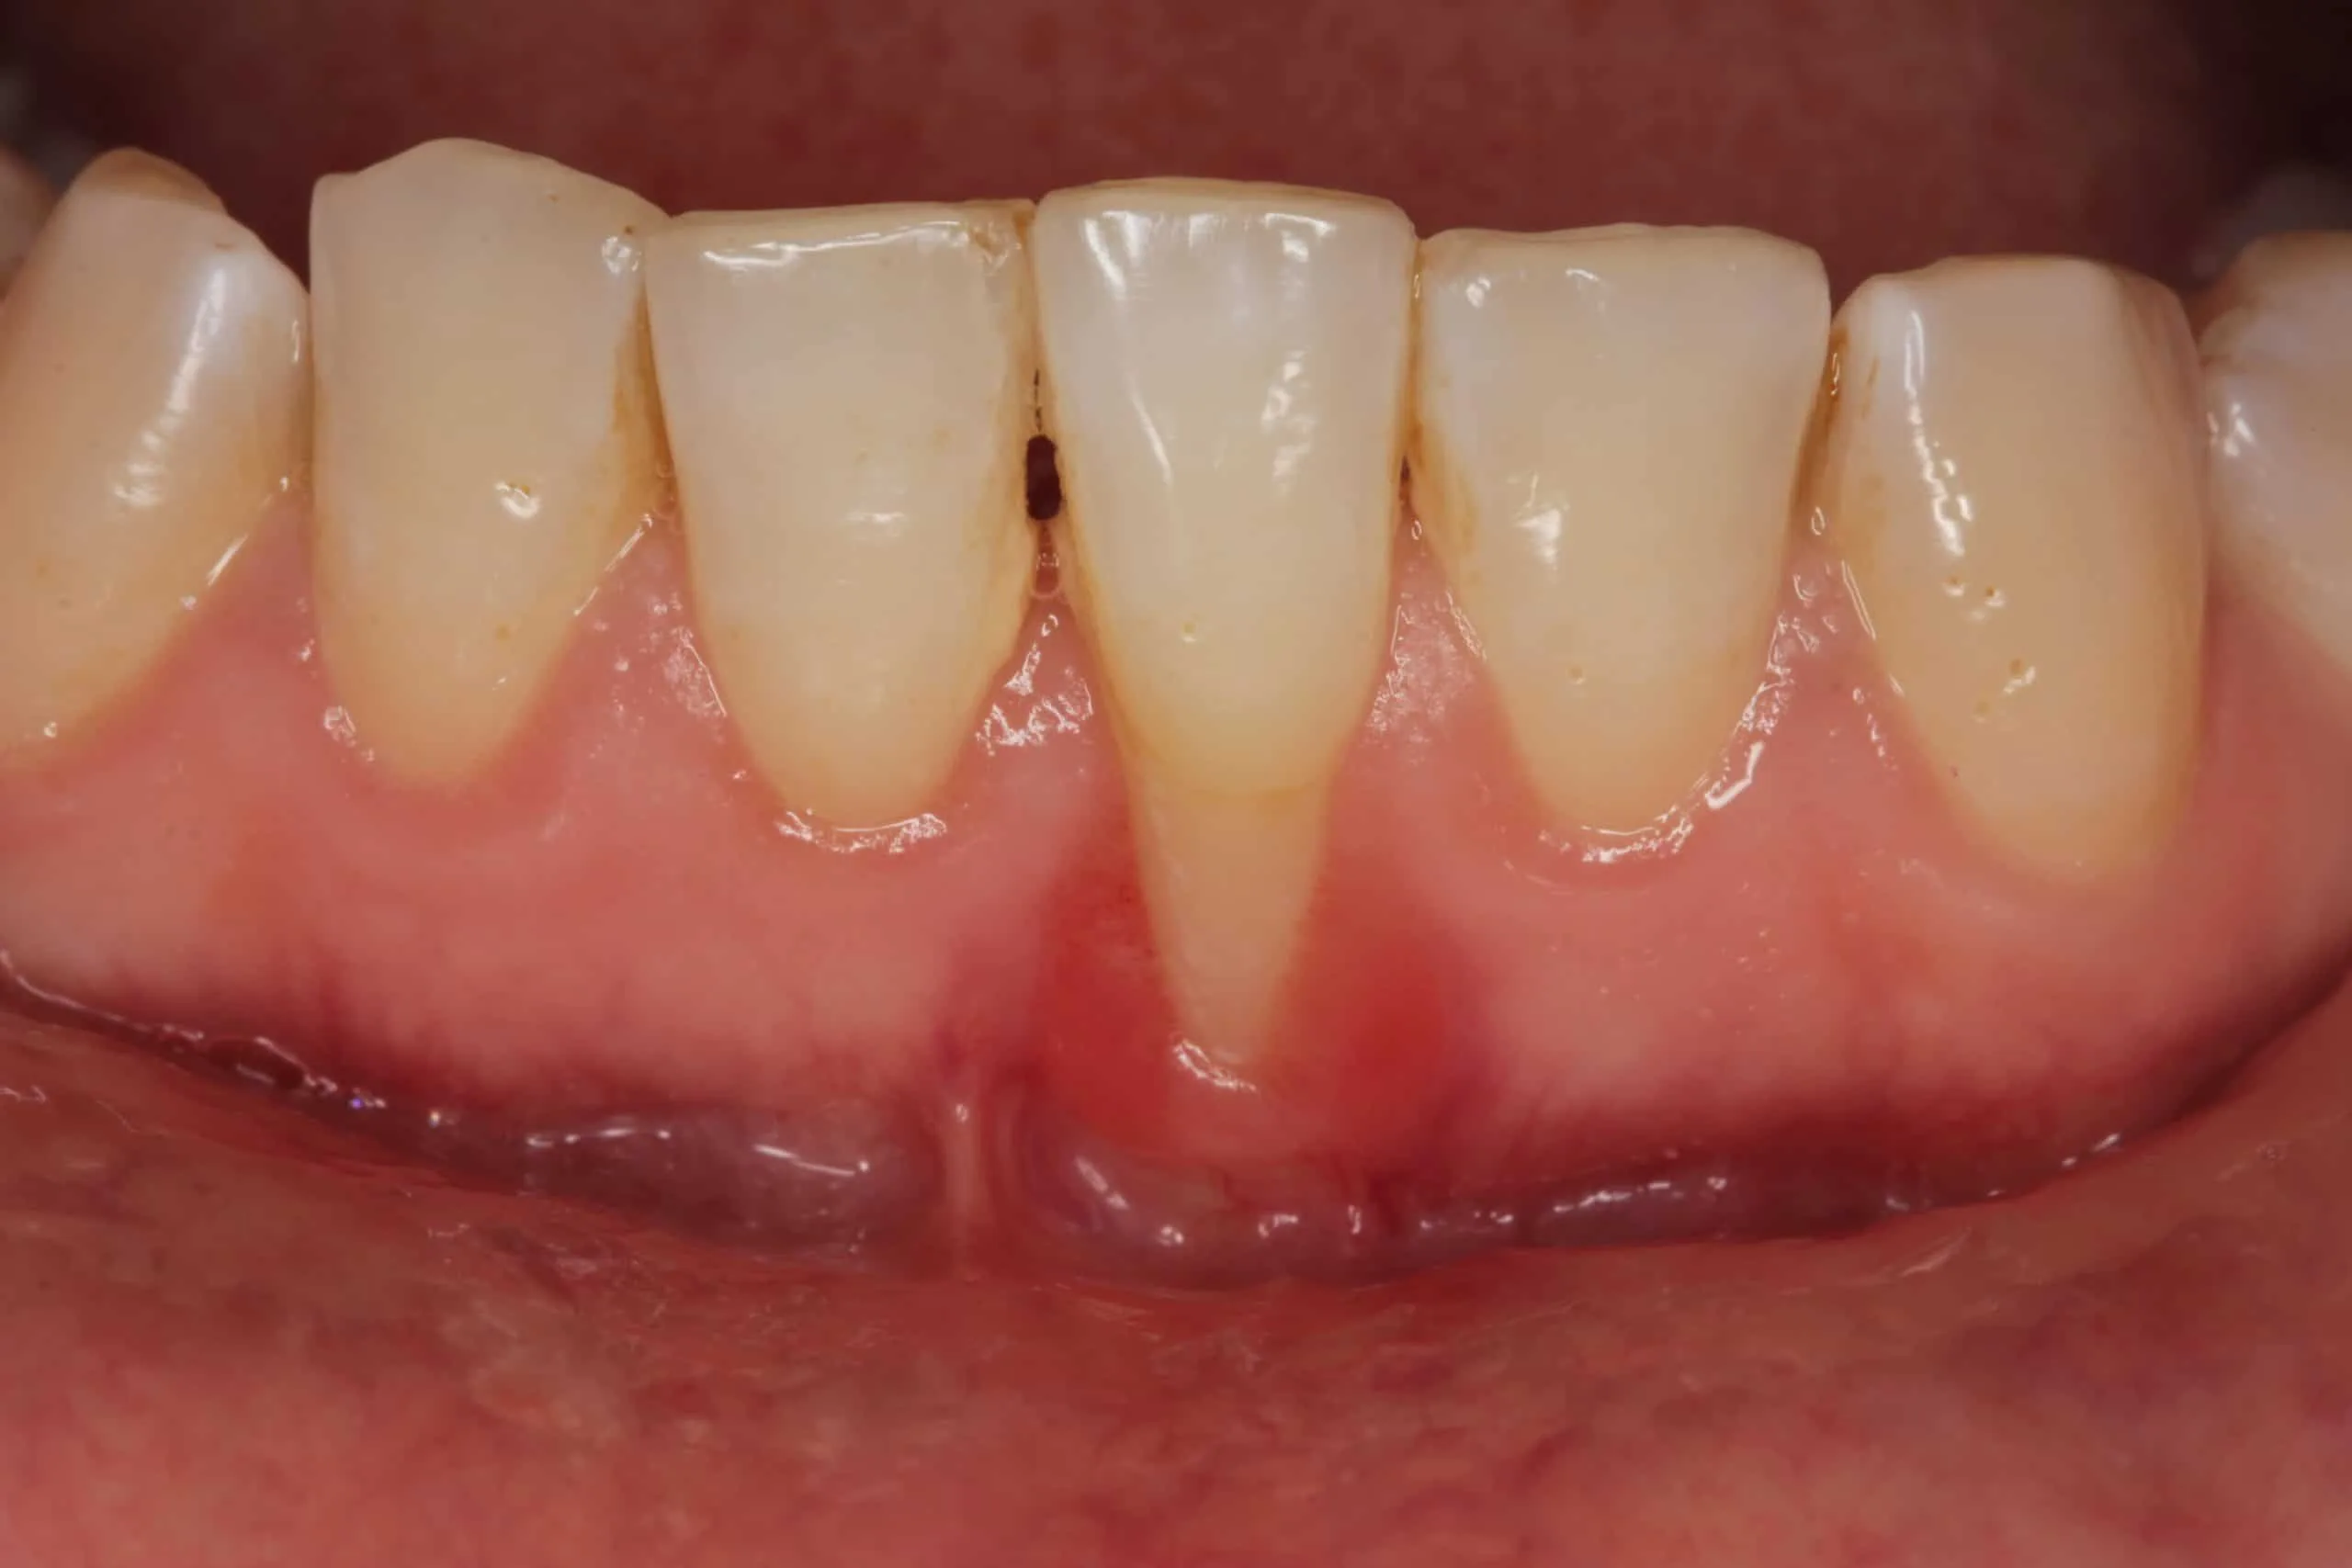

Retracción de encías grave

La retracción de encías grave es mucho más visible y problemática. Se expone una gran parte de la raíz, lo que suele venir acompañado de:

En estos casos, el tratamiento suele requerir técnicas quirúrgicas especializadas como injertos de encía para recuperar el tejido perdido.

En casos graves, cada día de retraso en el tratamiento puede significar más tejido perdido de forma irreversible.

Encias retraidas antes y despues